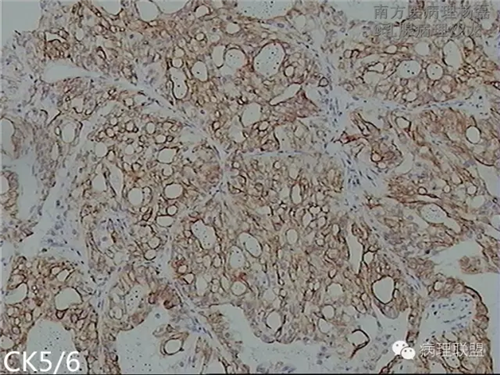

肺转移性乳腺分泌性癌?-病例讨论

女,51,右肺多发结节穿刺。15年前行右乳肿物切除,具体不详。